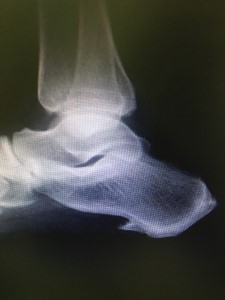

Calcaneal Spur